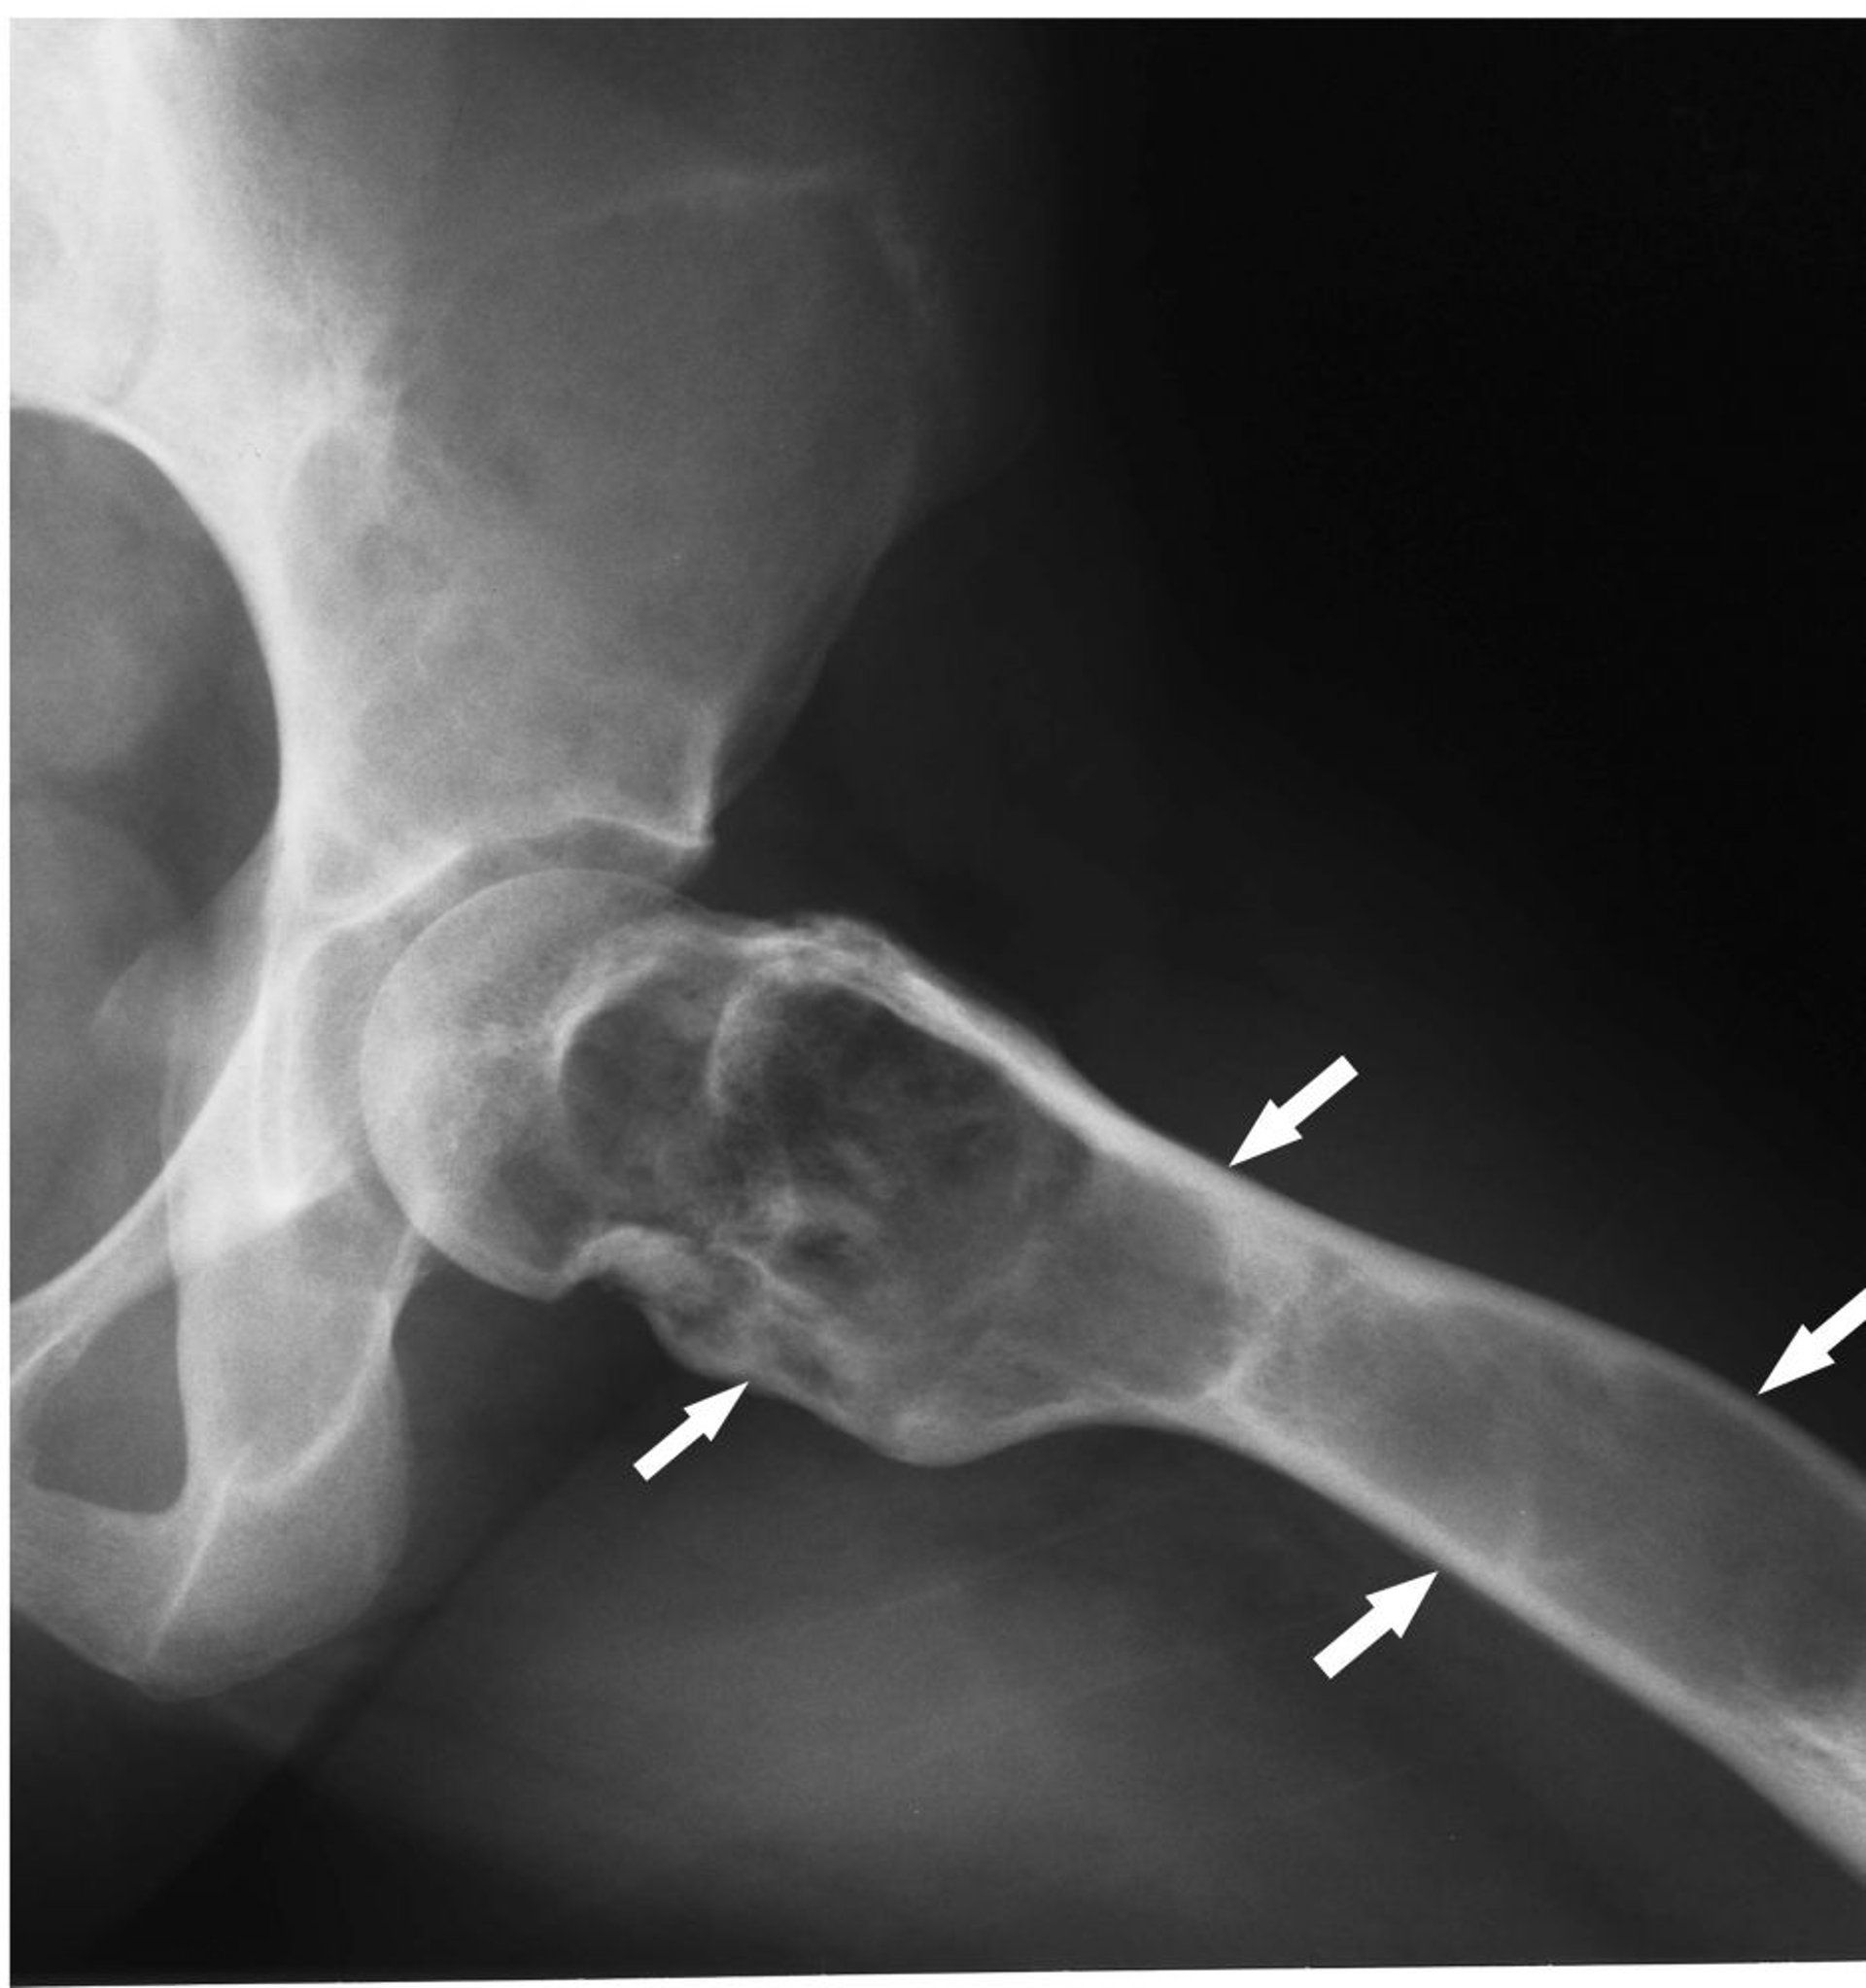

Esta radiografía de la cadera muestra displasia fibrosa (flechas) con expansión cortical y matriz de vidrio esmerilado.

Image courtesy of Michael J. Joyce, MD, and Hakan Ilaslan, MD.